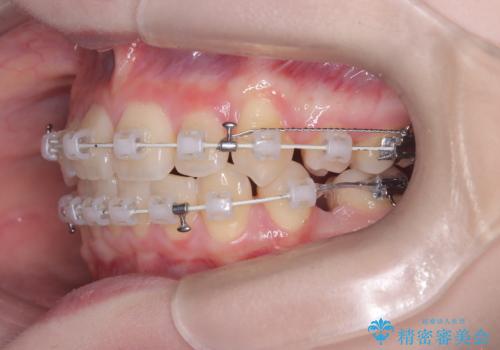

精密検査の結果、歯を並べるスペースの不足に加え、上下の歯列の正中(中心)が大きくズレていることが確認されました。突出した口元を下げ、顎の左右バランスを整えるためのスペースを確保するため、右上・左上・左下の4番目(第一小臼歯)を計3本抜歯する計画を立案。装置は、治療中の見た目にも配慮し、目立ちにくい審美ワイヤーを選択しました。

治療は、抜歯によって得られたスペースを活用し、前歯を後方へ移動させながら上下の中心を一致させる緻密な調整を行いました。

特に下顎の右方偏位に対しては、ワイヤーによる繊細なコントロールを行い、左右の咬合バランスを整えることに重点を置きました。2年半の治療期間を経て、突出していた前歯は理想的な位置に収まり、顎のズレも大幅に改善されました。